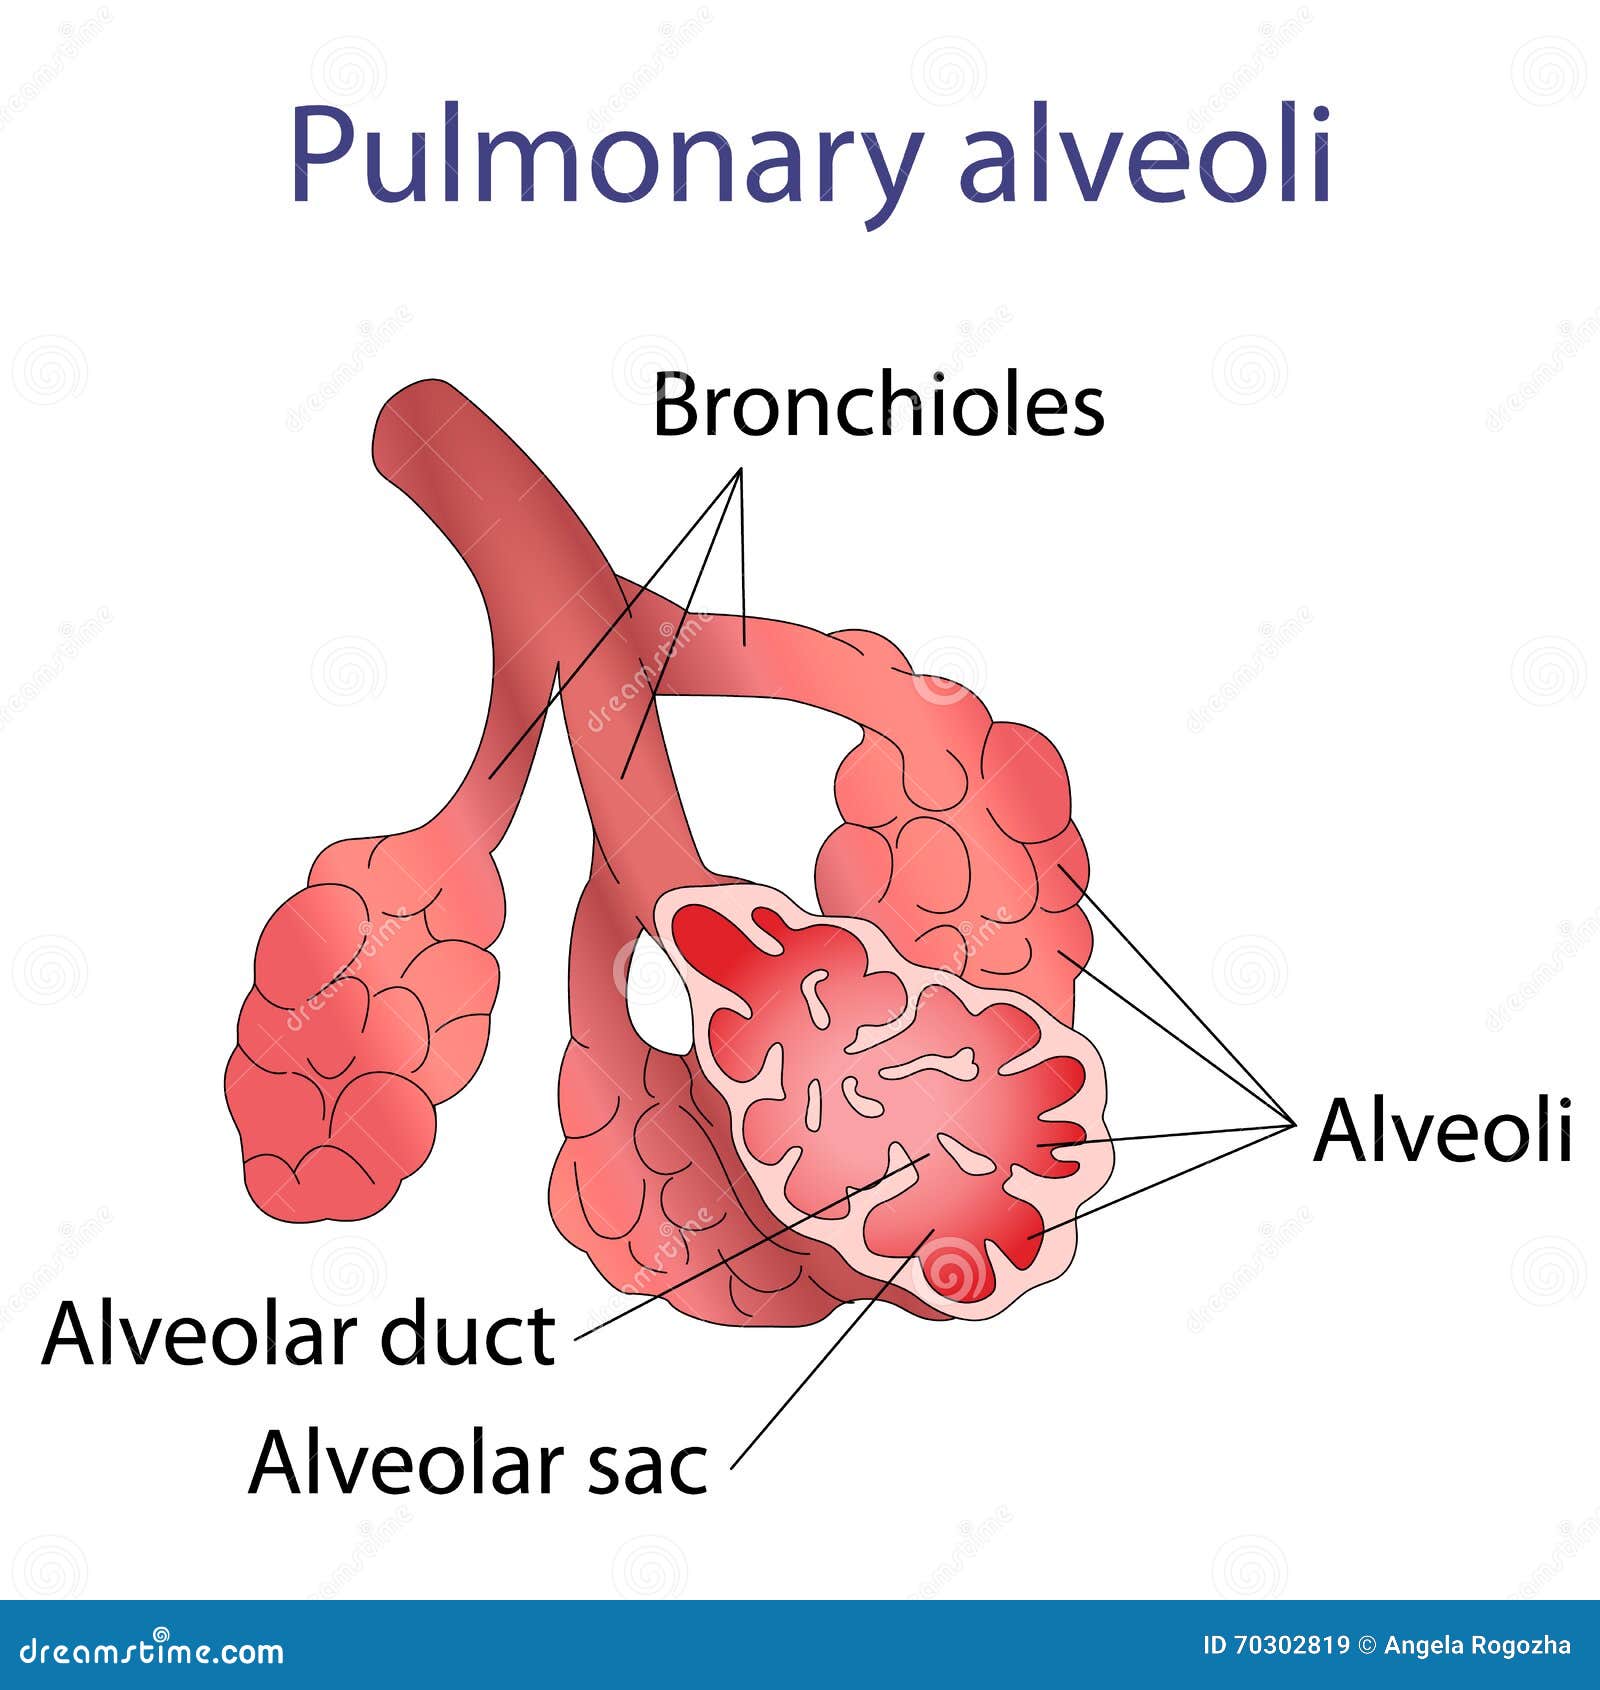

Alveolus Pulmonary ~ Nursing

nursing-skills.blogspot.com

nursing-skills.blogspot.com

alveolus pulmonary end